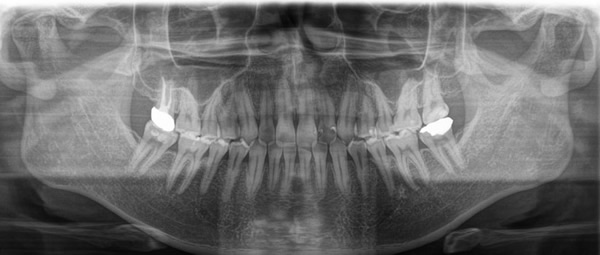

主訴:上下の歯並びのガタガタが気になる

診断名:上下顎叢生

症状:上下顎叢生

患者プロフィール:北九州市・小倉北区30代女性

治療方針:非抜歯治療

治療装置:マウスピース型矯正治療(インビザライン)

抜歯:無し

治療期間:一年半

通院回数:30回

リテーナー:上顎プレートタイプリテーナー 下顎フィクスタイプリテーナー

治療費用:検査診断料(20,000)+装置料金(500,000)+管理調整料(150,000) +装置撤去時診断料(10,000) +保定装置料金(20,000)=700,000(消費税込)

リスク副作用:痛み・治療後の後戻り・歯根吸収・歯髄壊死

詳しい症例説明:この患者さんはガタガタが気になり来院されました。マウスピースタイプの矯正装置で比較的短期間で治療を終えることができました。インビザライン(マウスピース矯正治療)で矯正治療を行うことで取り外して食事ができ、痛みもそれほど感じなかったとのことです。